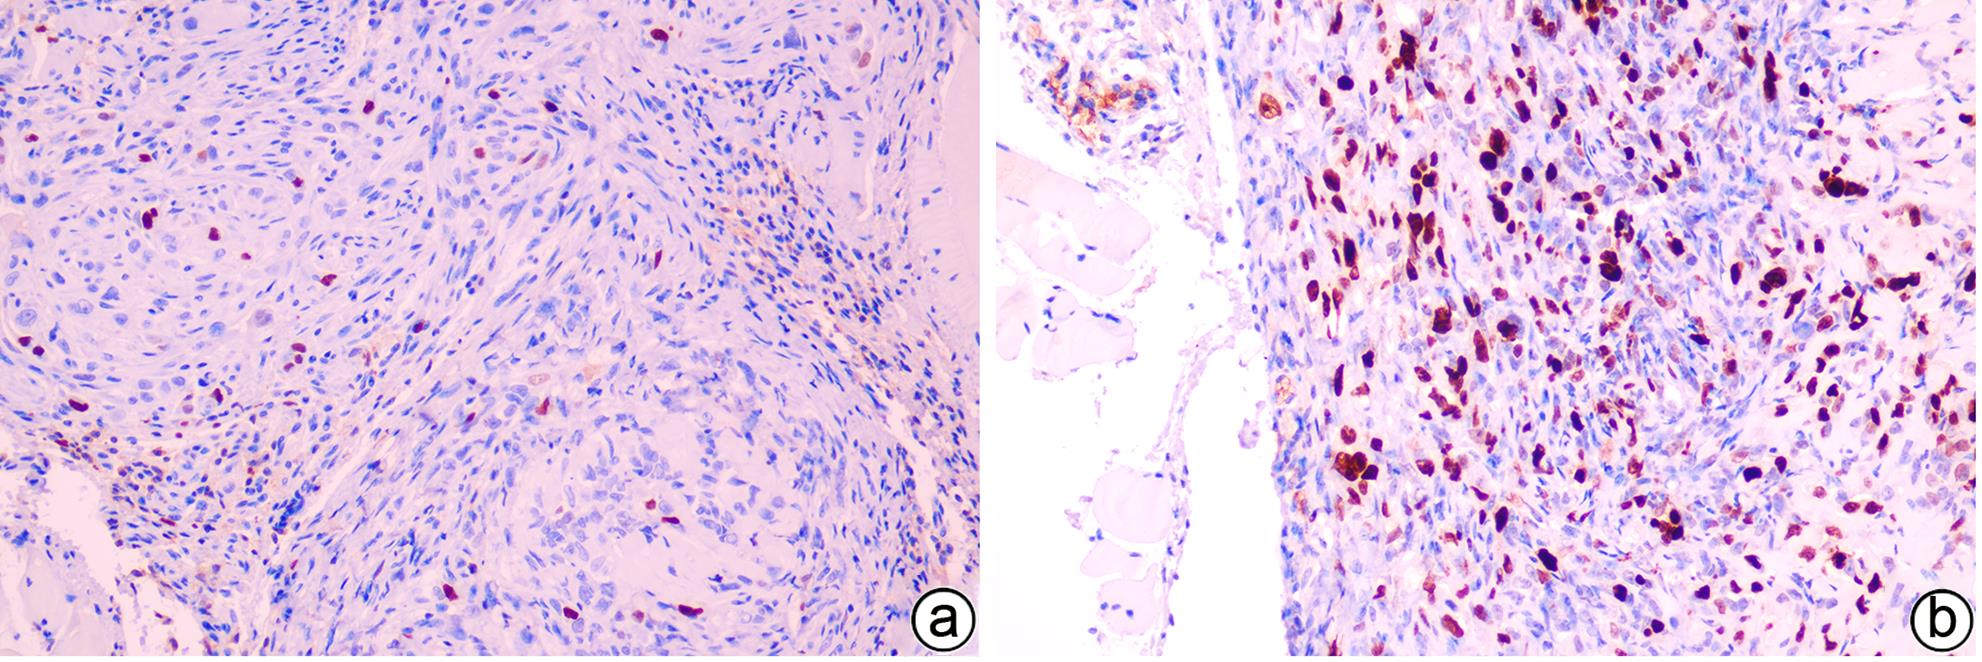

目的 建立可动态观察成瘤过程并进行体内研究的2型糖尿病(T2DM)胰腺癌裸鼠模型。 方法 首先,通过慢病毒载体GV260转染人胰腺癌细胞(PANC-1细胞)构建能稳定表达萤火虫荧光素酶的胰腺癌细胞株(PANC-1-Luc细胞)。然后,将36只SPF级裸鼠随机分为对照组(n=12,血糖正常的胰腺癌裸鼠)和模型组(n=24,T2DM胰腺癌裸鼠)。对照组:先给予繁殖饲料喂养,之后将PANC-1-Luc细胞异位种植于裸鼠皮下;模型组:先给予高脂饲料喂养联合腹腔注射1% STZ,之后将PANC-1-Luc细胞异位种植于裸鼠皮下。用荧光活体成像系统和人工测量法同步动态监测2组裸鼠胰腺癌生长情况,绘制肿瘤生长曲线、分析荧光值与肿瘤体积的关系。显微镜下观察裸鼠皮下肿瘤及胰岛,验证造模是否成功;同时,通过免疫组化检测肿瘤组织Ki-67的表达来分析高血糖对裸鼠胰腺癌生长的影响。正态分布计量资料组间比较采用成组t检验,非正态分布计量资料组间比较采用Mann-Whitney U检验。 结果 确定PANC-1细胞慢病毒载体稳定转染的最佳病毒滴度为5×107 TU/mL,用嘌呤霉素筛选的最佳浓度为20 μg/mL、最佳筛选时间为9天;PANC-1-Luc细胞的荧光值与细胞数量呈线性正相关,线性方程为y=42.56x-42 504(r=0.977,P=0.004)。T2DM裸鼠模型血糖值为23.05(19.25~26.40)mmol/L,且每只裸鼠的血糖均高于11.1 mmol/L,与对照组裸鼠血糖值[6.15(5.20~7.30)mmol/L]相比,差异有统计学意义(Z=-8.45,P<0.001)。与对照组相比,模型组胰腺组织内胰岛数量减少、体积减小、形状不规则、边界模糊,同时移植瘤病理学检查确认镜下为胰腺癌组织,可判定T2DM裸鼠胰腺癌模型造模成功。模型组皮下肿瘤大小与荧光值呈线性正相关,线性方程为y=232 348 691x-8 258 608(r=0.911,P=0.031);模型组移植瘤Ki-67免疫组化阳性率显著高于对照组[(50.333±7.808)% vs (15.917±4.055)%,t=13.55,P<0.001],说明模型组肿瘤增殖较快。 结论 本研究所构建的T2DM裸鼠胰腺癌模型可模拟T2DM背景下胰腺癌发生、发展的病理过程,动态观察高血糖对体内胰腺癌细胞生长的影响,从而为T2DM背景下胰腺癌发生、发展的体内研究提供新的实验载体。 Abstract:Objective To establish a nude mouse model of type 2 diabetes mellitus (T2DM) and pancreatic cancer that allows dynamic observation of tumor formation process and facilitates in vivo research. Methods At first, human pancreatic cancer PANC-1 cells were transfected with lentiviral vector GV260 to construct the pancreatic cancer cell line PANC-1-Luc with stable expression of firefly luciferase. Then, 36 specific pathogen-free nude mice were randomly divided into control group with 12 mice and model group with 24 mice (nude mice with T2DM and pancreatic cancer). The mice in the control group were fed with breeding diet and were then given ectopic subcutaneous implantation of PANC-1-Luc cells, and those in the model group were first given high-fat diet and intraperitoneal injection of 1% STZ, followed by ectopic subcutaneous implantation of PANC-1-Luc cells. The fluorescence in vivo imaging system and the manual measurement method were used for simultaneous and dynamic monitoring of the growth of pancreatic cancer in nude mice in the two groups, and the tumor growth curve was plotted to investigate the correlation between fluorescence value and tumor volume. Subcutaneous tumors and pancreatic islets were observed under a microscope to verify whether the model was successfully established, and immunohistochemistry was used to measure the expression of Ki-67 in tumor tissue to investigate the influence of hyperglycemia on the growth of pancreatic cancer in nude mice. The independent-samples t test was used for comparison of normally distributed continuous data between groups, and the Mann-Whitney U test was used for comparison of non-normally distributed continuous data between groups. Results The optimal virus titer was determined as 5×107 TU/mL for the stable transfection of lentiviral vector in PANC-1 cells, and the optimal concentration selected with puromycin was 20 μg/mL, with an optimal selection time of 9 days. The fluorescence value of PANC-1-Luc cells was linearly and positively correlated with the number of cells, with the linear equation of y=42.56x-42 504 (r=0.977, P=0.004). The blood glucose value of T2DM nude mice was 23.05 (19.25 — 26.40) mmol/L, with a blood glucose level of >11.1 mmol/L in each nude mouse, and there was a significant difference in blood glucose value between the T2DM nude mice and the control nude [6.15 (5.20 — 7.30) mmol/L] (Z=-8.45, P<0.001). Compared with the control group, the model group had reductions in the number and volume of pancreatic islets, with irregular shapes and unclear boundaries, and pathological examination confirmed that the xenograft tumor was pancreatic cancer tissue, which showed that the model was established successfully. In the model group, there was a linear positive correlation between subcutaneous tumor size and fluorescence values, with the linear equation of y=232 348 691x-8 258 608 (r=0.911, P=0.031). The model group had a significantly higher positive rate of Ki-67 than the control group (50.333%± 7.808% vs 15.917%±4.055%, t=13.55, P<0.001), suggesting rapid tumor proliferation in the model group. Conclusion The T2DM nude mouse model of pancreatic cancer established in this study can simulate the pathological process of the development and progression of pancreatic cancer in the context of T2DM and dynamically observe the influence of hyperglycemia on the growth of pancreatic cancer cells in vivo, thereby providing a new experimental vector for the in vivo study of the development and progression of pancreatic cancer in the context of T2DM. -